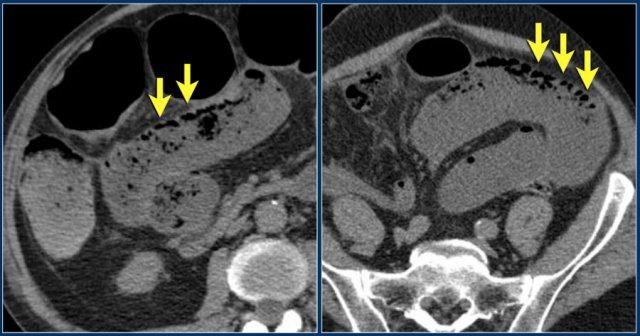

Các hình ảnh này thuộc về bệnh nhân bị tắc ruột non dạng quai kín.

Lưu ý nhóm các quai ruột non có thành dày ở vùng bụng trên phải (mũi tên vàng).

Phù nề mạc treo ruột (mũi tên đỏ) cho thấy tình trạng tăng áp lực tĩnh mạch do thắt nghẹt.

Giãn mạch máu

Tăng áp lực tĩnh mạch trong thắt nghẹt cũng dẫn đến giãn tĩnh mạch (mũi tên vàng).

Bệnh nhân này cũng có tắc ruột dạng quai kín với kiểu ngấm thuốc xám của các quai ruột bị thắt nghẹt (mũi tên đỏ).

Lưu ý sự ngấm thuốc bình thường của ruột non ở phía trên vị trí tắc nghẽn (mũi tên xanh lá).

Một bệnh nhân khác với hình ảnh ruột thiếu máu cục bộ và phù nề mạc treo ruột lan rộng.

Trong phẫu thuật, toàn bộ đoạn ruột non này đã bị hoại tử.